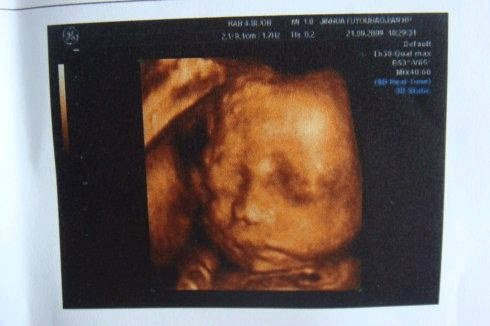

30周4天的小排畸检查

而小排畸的检查方式一般会使用高分辨力的彩色多普勒血流显像仪检查,主要是四维彩超一般黑白B超只要求进行上述常规超声检查内容,一般不用黑白B超进行详细系统胎儿畸形超声检查。

小排畸检查在30周左右

一般大排畸都是采用的四维彩超检查,主要观察染色体异常标记,监测胎儿在宫内的发育情况。而小排畸只需做普通B超就可以,因为此时胎儿已经到了孕晚期,通过普通B超就能看到是否存在异常。

一般来说在孕30周做的小排畸用黑白二维B超就可以了,只有在大排畸的时候才会考虑用三维或者四维彩色B超,因为此时宝宝不是很大,只有三维(四维)彩超,看得比较清楚。再有就是大家提到的二维超声、三维超声和四维超声只是一种设备技术的变革,对于孕期的畸形筛查来说,三种超声是没有实质区别的,主要是超声医师的能力和水平。